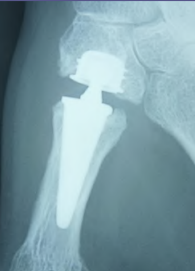

Prothèse trapézométacarpienne

Prothèse totale de pouce